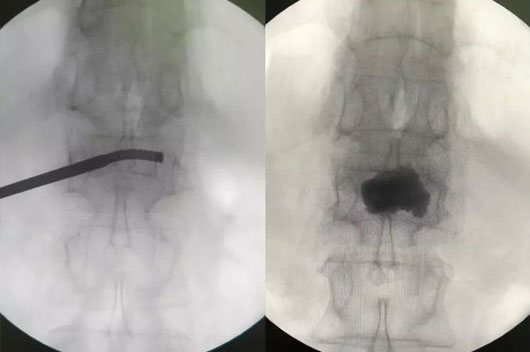

´Ë´ÎÊÖÊõʹÓûúеÈËÍýÏëµ¥²à´©´ÌÑü1×ó²àõè¾¶£¬£¬£¬£¬£¬£¬£¬£¬Çпª0.5cmƤ·ô£¬£¬£¬£¬£¬£¬£¬£¬ÔÚ»úе±ÛÖ¸µ¼Ï¾«×¼ÖÃÈëµ¼Õ롢ͨµÀÖÁ×µÌåÄڵİÐλÖ㬣¬£¬£¬£¬£¬£¬£¬°²ÅÅ¿ÉÍäÇúÇòÄÒ¾ÙÐж¨µãÀ©ÕÅÅòÕÍ£¬£¬£¬£¬£¬£¬£¬£¬Ë³ËìÍê³É¿ÉÍäÇúµ¥²àPKPÊÖÊõ£¨Í¼1-4£©¡£¡£¡£¡£¡£

ͼ3£¬£¬£¬£¬£¬£¬£¬£¬ÍÆ×¢¹ÇË®Äà

ͼ4£¬£¬£¬£¬£¬£¬£¬£¬µ¥²à´©´ÌÖÁ×µÌå¶Ô²à½¨É軡ÐÎͨµÀ£¬£¬£¬£¬£¬£¬£¬£¬¹ÇË®ÄàÂþÑÜÓÅÒì